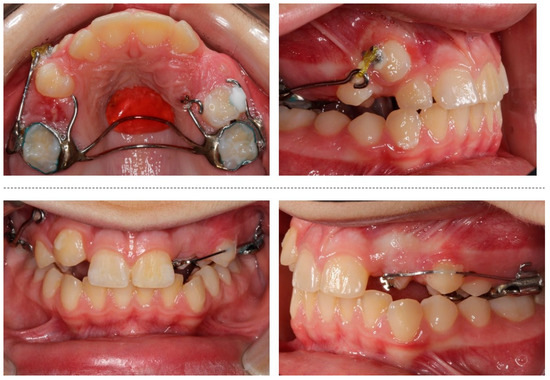

The orthodontic treatment was initiated with the canine exposure (Figure 5) and traction with light forces using a custom-made trans-palatal arch for anchorage purposes (Figure 6 and Figure 7). An open surgical technique (apically positioned flap) was used to expose the labially positioned right canine and a closed technique for the left, which was positioned palatally. Sectional mechanics were applied during treatment until the eruption of all permanent teeth (Figure 8). The upper lateral incisors were extracted after the successful eruption of the impacted canines and for aesthetic reasons. Subsequently, comprehensive orthodontic treatment was performed using fixed 0.018-inch-slot edgewise appliances. A lower lingual arch was placed to preserve the leeway space thus helping with the lower crowing. The progression of the archwire sequence was from 0.014-inch nickel-titanium to 0.016-inch Australian archwires. Class III light elastic forces were used bilaterally to help with space closure on the upper arch.

The dental age and the adverse tooth prognosis in this patient necessitated the use of a custom made trans-palatal arch for the traction of the canines. This arch was bonded on the permanent first molars, as well as the palatal and buccal surfaces of the right and left deciduous second molars, respectively. The appliance was further stabilized on the hard palate mucosa with an acrylic button. This design allowed the even distribution of the reciprocal forces during the canine traction on the aforementioned structures.

Figure 7. Progress photographs of the custom-made trans-palatal arch used for the traction of the impacted canines.

Figure 8. Sectional mechanics used for the traction of the impacted canines.